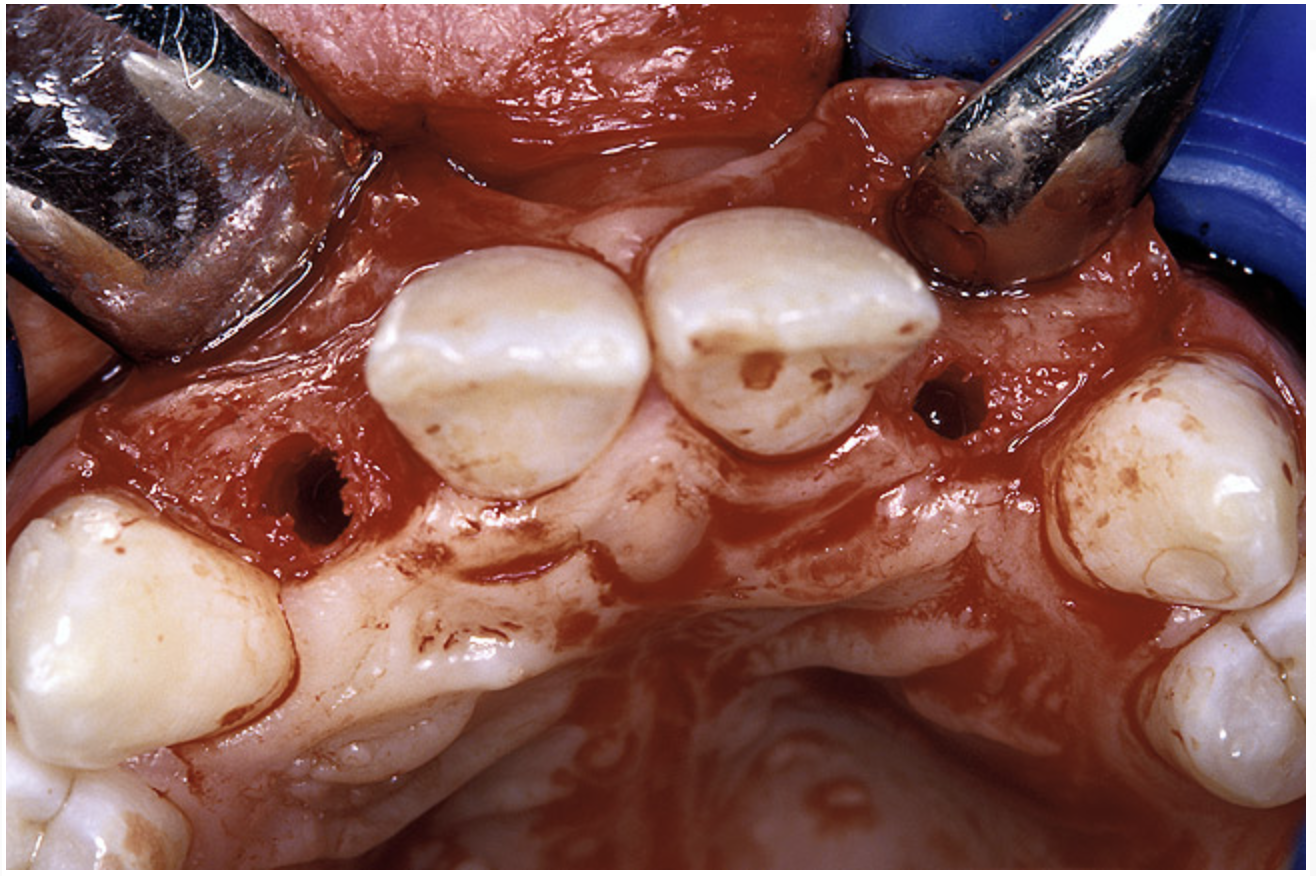

Before the day of surgery, the patient was seen by the orthodontist for the removal of the orthodontic brackets. The patient still was not pleased with the position of the two centrals, and it was determined that this would be addressed after implant placement (Figure 13A). The anatomical variations of the crestal tissue and lack of interdental papilla can be appreciated in the close-up views of the right and left sites (Figure 13B and 13C). There were no surprises on the day of surgery as all of the decisions were made during the planning phase, before the scalpel ever touched the patient. The occlusal view of the CT 3D model revealed the wider alveolar ridge on the right side and thinner crest on the left side (Figure 14A). This was confirmed when the full thickness mucoperiosteal flaps were elevated, and the underyling bone revealed (Figure 14B). The tooth-borne templates were designed to facilitate the drills and drilling sequence specific to the diameters of the predetermined implants (Figure 15A). Each template contained an embedded 5-mm long stainless steel tube, which was approximately 0.2-mm wider than each drill (just wide enough to allow for the drills to rotate freely). Once positioned over the natural teeth, the template was secure and offered precision accuracy in transferring the implant locations from the original software-designed plan, allowing the potential for internal and external irrigation (Figure 15B).

Figure 14a  The information gained from (A) the 3D model was confirmed when (B) the flaps were elevated.

Figure 14a

Figure 14b  The information gained from (A) the 3D model was confirmed when (B) the flaps were elevated.

Figure 14b